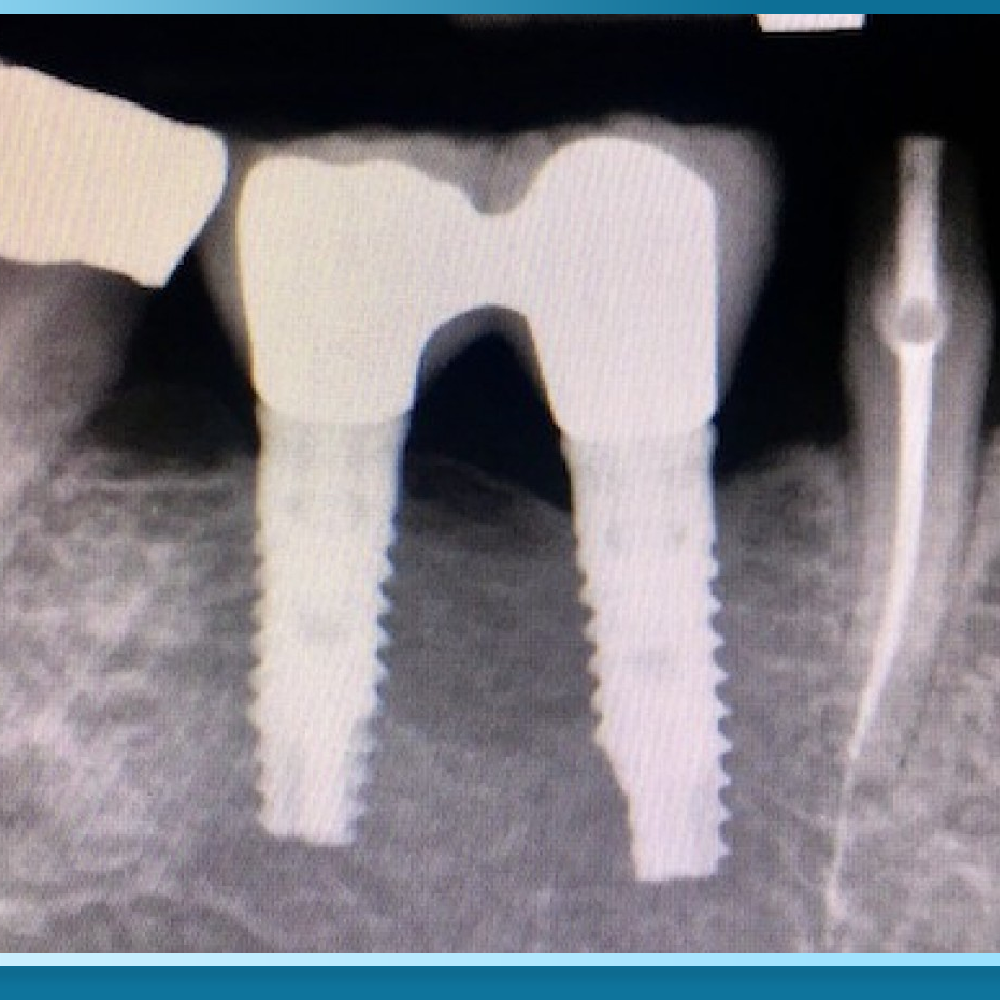

Do đó, việc xác định mức độ viêm nhiễm thông qua phim chụp CT Cone Beam 3D là bước đi tiên quyết để xây dựng một phác đồ điều trị an toàn và hiệu quả trước khi tiến hành phẫu thuật.

Tần suất tái khám định kỳ đối với bệnh nhân có tiền sử viêm nha chu cần được thực hiện gắt gao hơn so với người bình thường, đặc biệt là trong năm đầu tiên sau cấy ghép. Bác sĩ sẽ tiến hành vệ sinh chuyên sâu, kiểm tra độ khít sát của các vít kết nối và theo dõi mức độ ổn định của xương hàm qua phim chụp X-quang.